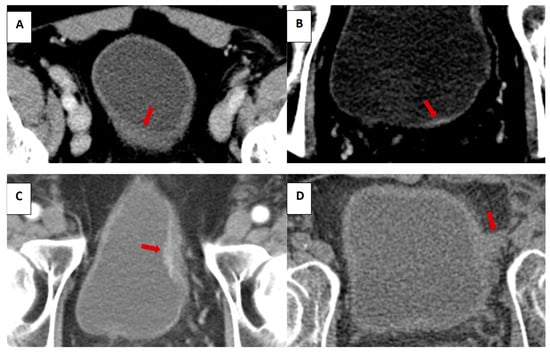

3. Results